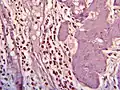

Histopathology

Histopathology is indicated if preoperative imaging and/or gross examination gives a suspicion of gallbladder cancer.[29]

Histopathology of eosinophilic cholecystitis

Histopathology of eosinophilic cholecystitis -